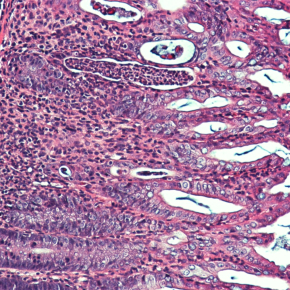

Les inflammations de l’intestin touchent de nombreux patients, avec des perspectives thérapeutiques souvent réduites. Le rôle du fer dans ces processus inflammatoires est de mieux en mieux documenté, permettant d’ouvrir de nouvelles pistes de traitements. Une étude collaborative entre l’équipe dirigée par la directrice de recherche Inserm Carole Peyssonnaux à l’Institut Cochin (Inserm/CNRS/Université de Paris) et l’équipe de Greg Sonnenberg à New York (Weill Cornell Medicine) montre que l’hormone qui régule le niveau de fer dans l’organisme est produite par des cellules immunitaires lors d’une inflammation de l’intestin, et qu’elle contribue à réparer les lésions de la muqueuse intestinale. Ces travaux sont publiés dans la revue Science.